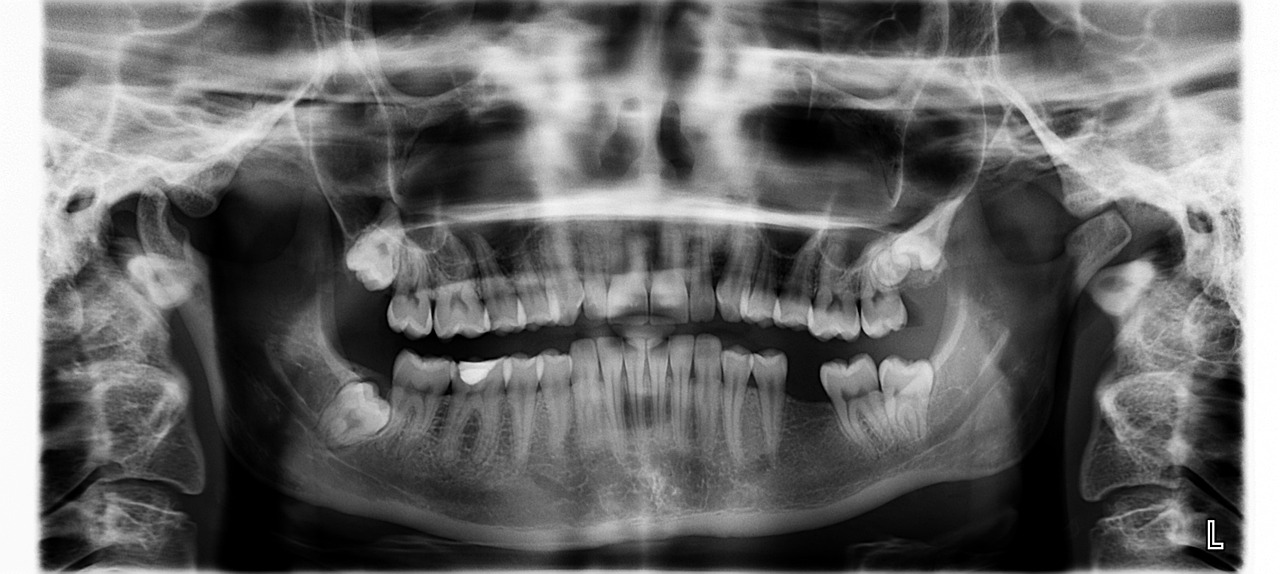

3) 영상 검사

- X-ray : 구강 및 턱의 뼈 구조를 확인하는 데 사용됩니다.